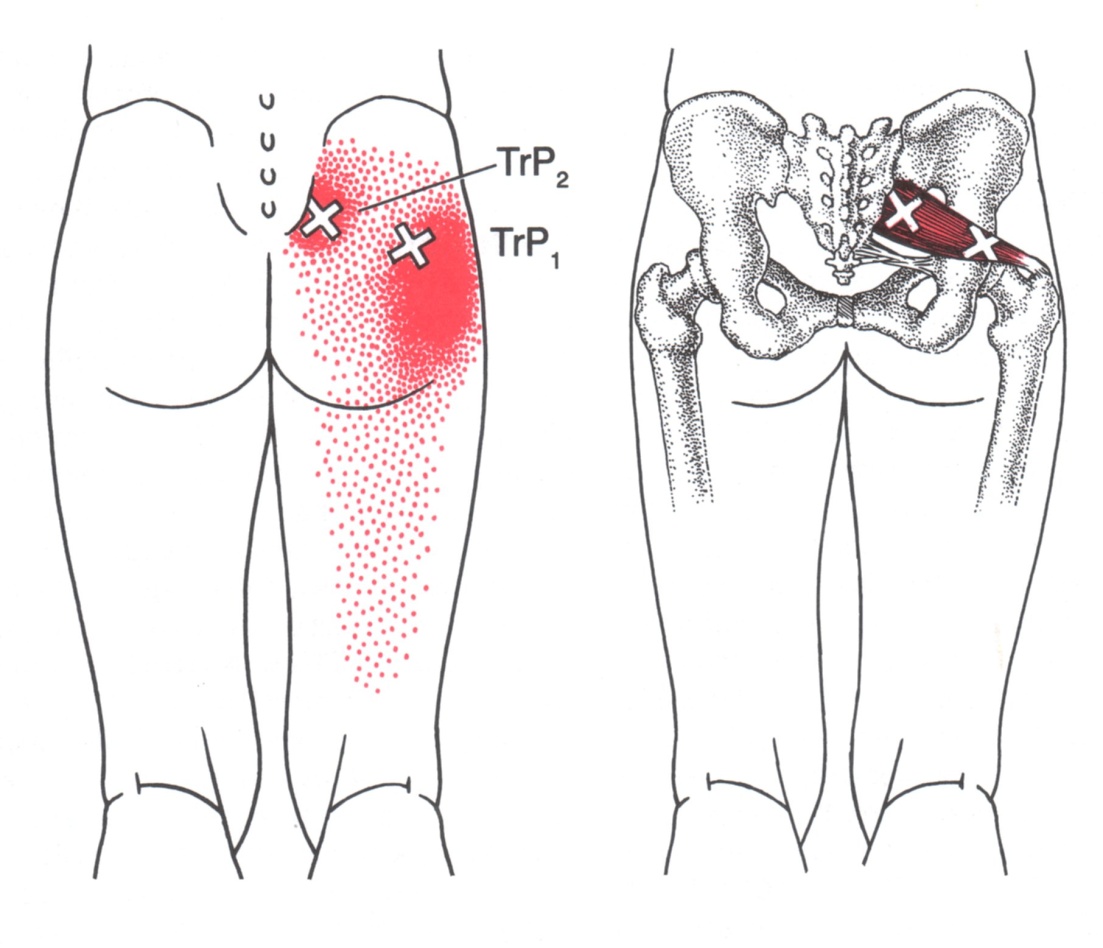

Piriformis Trigger Point Diagram 이상근의 TrPs의 경우 방사통은 천장관절부로 방사되기도 하며,

외측으로는 둔부 중앙을 넘어 고관절 후부와 대퇴 후부의 근위부 2/3로 방사됩니다.

넘어지려할 때 중심을 잡으려고 체중을 지탱하고 있는 다리를 급격히 내회전시킬 때(예를 들면, 달리기 하는 동안)와 같은 급성 과부하에서 초래됩니다.

차를 운전할 때 장시간 동안 대퇴를 외전 및 굴곡된 상태를 유지하는 것과 같은 지속적인 과부하는 이들 TrPs를 지속화시킵니다.

내측의 TP는 자침시 좌골신경을 맞출 가능성이 높아 가급적 외측만 자침(-Neck방향으로 자침)하며,

골반의 모양차이로 인해 남성이 여성보다 조금 더 높게 위치하는 경우가 많습니다.